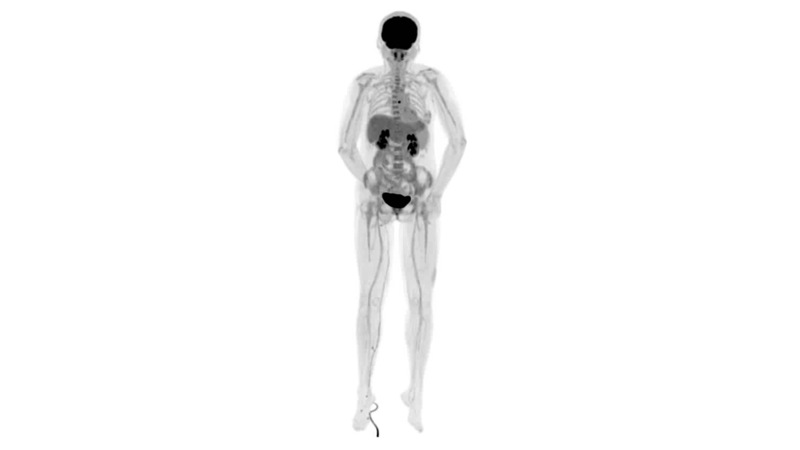

uExplorer探索者不再局限于傳統(tǒng)靜態(tài)代謝過(guò)程3D成像,而是在此基礎(chǔ)上新增一個(gè)維度——時(shí)間,從而實(shí)現(xiàn)4D全景成像。

注射總劑量為7.8mCi,14分鐘全身采集時(shí)間,在擁有超高靈敏度與超高分辨率的uEXPLORER上,即可得到展示顯示人體諸多精細(xì)結(jié)構(gòu)的高清三維圖像。

注射總劑量為7.8mCi,注射后1.6小時(shí),基于uEXPLORER探索者掃描1分鐘的圖像

注射總劑量為0.67 mCi FDG(低于常規(guī)劑量的十分之一),基于uEXPLORER探索者掃描15分鐘的圖像

注射總劑量為6.9mCi,注射后10小時(shí),基于uEXPLORER探索者掃描14分鐘的圖像